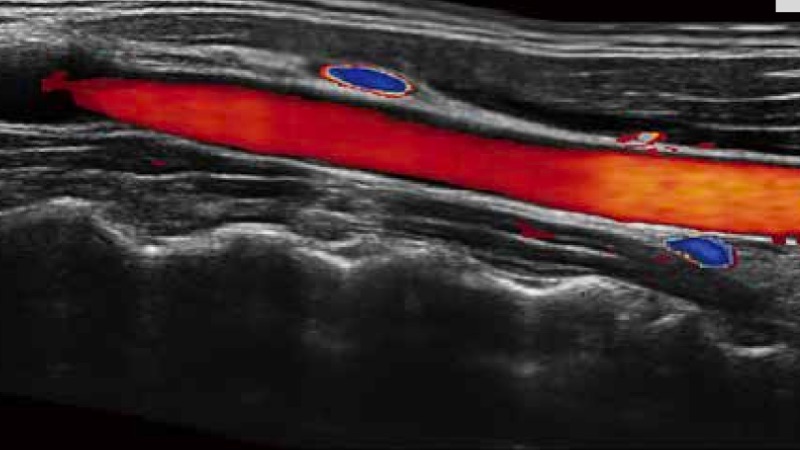

開(kāi)立醫(yī)療通過(guò)不斷的技術(shù)創(chuàng)新,為大眾的生命健康提供持續(xù)關(guān)愛(ài)。P12 Plus采用全新一代超聲成像平臺(tái),新平臺(tái)旨在將真實(shí)還原組織解剖結(jié)構(gòu)作為首要目標(biāo)。平臺(tái)采用全新集成化硬件模塊,搭載新一代芯片,系統(tǒng)性能得到大幅提升,為您的診斷提供了豐富的臨床信息。優(yōu)異的圖像表現(xiàn),豐富的探頭配置,全面的應(yīng)用功能,為您日常診斷提供了可靠的助手。

彩色多普勒超聲診斷系統(tǒng)